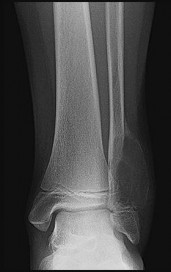

Figures 9a through 9d are the anteroposterior and lateral radiographs, CT scan, and technetium bone scan of a 12-year-old boy who has experienced 7 months of pain in his lower leg. The pain limits his ability to participate in sports and he is having difficulty sleeping. He is afebrile, and laboratory study findings including an erythrocyte sedimentation rate, C-reactive protein, and complete blood count are within normal limits.

The images and clinical history support a diagnosis of osteoid osteoma, which most commonly occurs in adolescence. Although these lesions can be seen in any bone, they are usually located in the femur and tibia. The significant inflammatory response to this tumor is secondary to high levels of prostaglandin production. Characteristic night pain is relieved with nonsteroidal anti-inflammatory drugs (NSAIDs) or by aspirin.

Radiographic images show thickened bone and a small central nidus. Thin-cut CT scan is the imaging of choice to visualize the nidus. A bone scan is associated with uptake but is not specific. Treatment options include expectant management with NSAIDs and observation under the premise that these lesions eventually burn out. Contemporary treatment involves RFA. Historically, these lesions were treated with en bloc resection; however, this technique has largely fallen out of favor because of the high efficacy and comparative low morbidity associated with RFA.

When an osteoid osteoma occurs in the spine, it is located in the posterior elements, and paraspinal pain and scoliosis often are present.